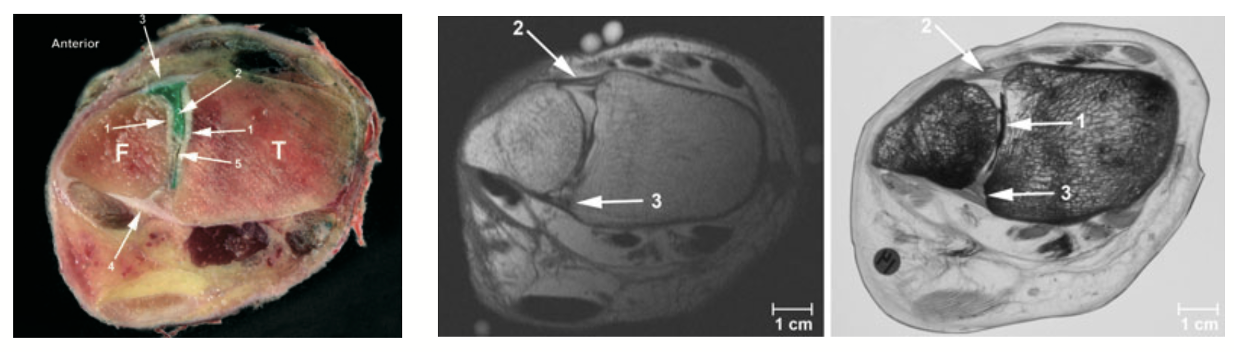

The ligament most commonly injured is the anterior inferior tibiofibular ligament (AITFL) — the ligament running across the front of the joint between the tibia and fibula. In more severe injuries, the deeper interosseous ligament (IOL) and the fibrous sheet running the length of the lower leg (the interosseous membrane) may also be disrupted.

•       MRI scan: The best investigation to confirm which ligaments are torn and grade the severity. MRI also detects cartilage injury inside the ankle joint, which is a recognised consequence of syndesmotic instability. The one problem with MRI scan is that it is not a dynamic (weight bearing) test, this is where WBCT comes in.